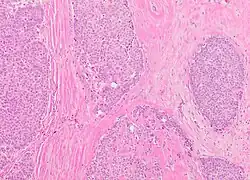

Microscopic histopathological analyses of SPC lesions (refer to adjacent high-power photomicrograph) generally show tumors with multiple circumscribed nodules of expanded ducts filled with neoplastic epithelial cells which may appear spindle-shaped or plasma cell-like, have red to pink cytoplasm due to the uptake of eosin after staining with hematoxilin & eosin, and eccentrically-placed nuclei. Rarely, signet ring-shaped cells are present. The tumors may have cystic and hemorrhagic areas. Myoepithelial cells are found within and at the periphery of these tumors. The papillary architecture seen in the other SCB types is in general not apparent; rather, pseudo-rosettes (i.e. radial arrangements of neoplastic cells around small blood vessel) and nuclear palisading (i.e. parallel arrangements of the nuclei in rows of tumors that resembles picket fences) around stromal cores (i.e. supporting tissues) may be seen. SPC tumor tissues typically (>50% of cases) have areas of neuroendocrine differentiation. The presence of these areas strongly supports the diagnosis of SPC.[21] The signet ring-shaped cells in these tumors contain cytoplasmic mucin-containing vacuoles which push their cells' nuclei to one side.[10] Mucin may also occur outside of cells in these lesions. The presence of signet ring-shaped cells bearing mucin-containing vacuoles with or without extracellular mucin strongly supports the diagnosis of SPC. SPC is considered invasive when the tumor nests have a characteristic jigsaw growth pattern with ragged and irregular margins with the loss of myoepithelial cells at the site(s) of invasion.[21] Rarely, invasive SPC occurs with nearby invasive carcinoma of NST, lobular carcinoma, cribriform carcinoma, or tubular carcinoma breast tumors.[3]